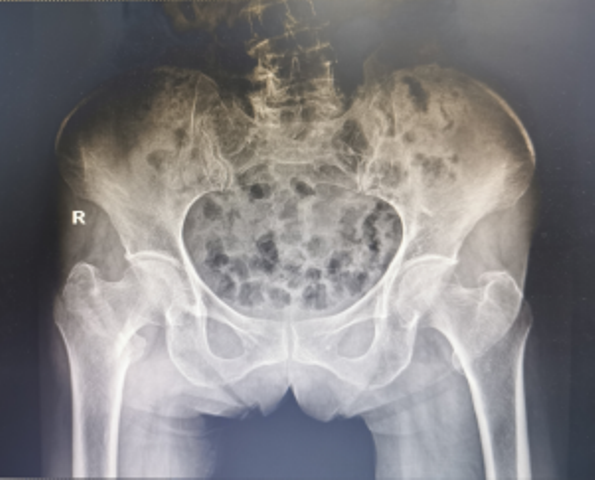

3月19日,91岁高龄的万奶奶在家行走的时候不慎摔倒在地,当即感到右髋部剧烈疼痛,且不能行走。家属赶紧拨打21点基本策略 120急诊电话,随后收治骨一科治疗,经检查确诊:右股骨粗隆间粉碎性骨折。

然而万奶奶患有冠心病、腔隙性脑梗塞、贫血等老年基础病史,手术治疗非常棘手。